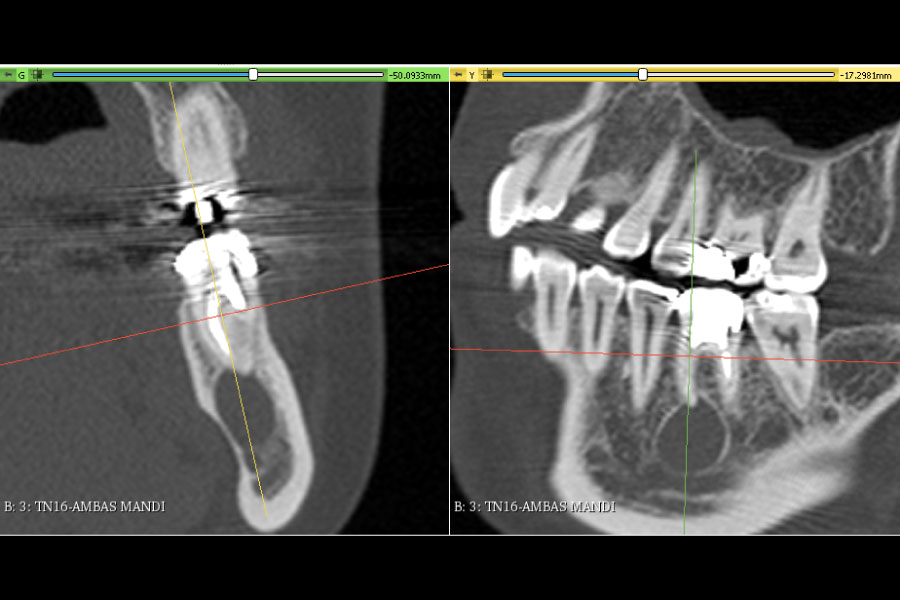

A la hora de importar todas estas mallas al software de planificación 3d Exacto, tenemos generalmente 3 opciones, (Alinear con el archivo Dicom, importar en el centro de la escena, importar en sus coordinadas originales).

Una de las formas, de poder alinear todas las mallas superiores (Modelo superior con esos, sin esos y encerado 15) con el archivo DICOM del maxilar superior sin que estas pierdan la correcta relación entre sí, es importar las 3 mallas en sus coordenadas originales. Una vez tengamos las mallas en 3D exacto, se creará un grupo con las 3 mallas liderado por la malla “Superior Inicial” (antes de las exodoncias virtuales) y será este modelo, el que usemos para alinear con el archivo DICOM del maxilar superior. Al estar dentro de un grupo, los otras 2 mallas (“modelo superior con extracciones” y “encerado 15”) quedaran también alineadas con el archivo DICOM.

Una vez confirmada la alineación entre el la malla “Superior Inicial” y el archivo dicho es correcta, ya tendremos todo listo para planificar nuestros implantes de manera convencional usando el encerado que hemos realizado previamente en Exocad y con un modelo con la extracción virtual realizada que podremos utilizar la confección de nuestra férula de cirugía guiada.